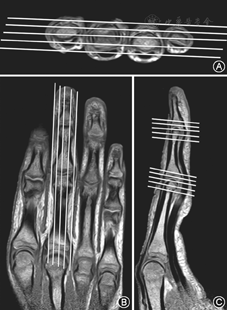

患者取俯卧位,手指尽量伸直,线圈尽量裹紧关节,行轴位、冠状位、矢状位三个方位的质子压脂序列(PD-FS序列)扫描和冠状位T1WI序列扫描(图1,图2)。扫描参数:PD-FS序列,TE=40~45 ms,TR=3 000~4 000 ms,层厚2 mm,层间距0.2 mm,层数12层;冠状位FOV 140 mm×100 mm,矩阵348×244;矢状位FOV 140 mm×70 mm,矩阵348×210;轴位FOV 100 mm×100 mm,矩阵332×305。T1WI序列,TE=20 mm,TR=500 mm,层厚2 mm,层间距0.2 mm,层数12~24层;冠状位FOV 140 mm×100 mm,矩阵348×200;矢状位FOV 140 mm×70 mm,矩阵348×141;轴位FOV 100 mm×100 mm,矩阵332×285。

20名正常志愿者的手指肌腱韧带结构在MR图像上均表现为细条状均匀低信号,肌纤维连续(图3)。侧副韧带在冠状位显示最佳;中央束、矢状束、末端腱及屈肌腱在矢状位和轴位显示最佳。